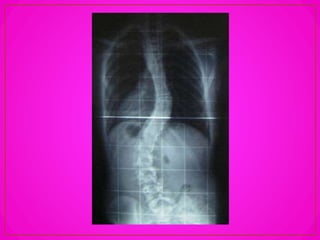

Escoliosis

Existe una leve curva de concavidad izquierda en la

región dorsal, como resultado del desigual desarrollo

muscular de la cintura escapular y del miembro

superior derecho. En los zurdos la concavidad es hacia

la derecha. Esta rectitud de la columna se puede

alterar por las siguientes causas:

– Desigualdad de longitud de los miembros

inferiores; en este caso, la pelvis se inclina hacia el

lado más corto, para conservar el equilibrio,

produciéndose escoliosis compensadora.

– Malformaciones congénitas (escoliosis

congénita).

– Parálisis de los músculos de los canales

vertebrales, como en la poliomielitis.

– En retracciones de un hemitorax por procesos

pleuro-pulmonares graves. Esta también es una

escolisis compensadora.